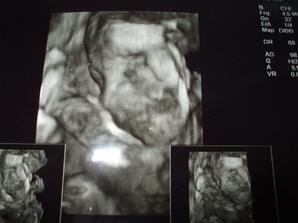

V piatok 30.5. sme sa dozvedeli, že v maminkinom brušku s najväčšou pravdepodobnosťou býva dievčatko 🙂